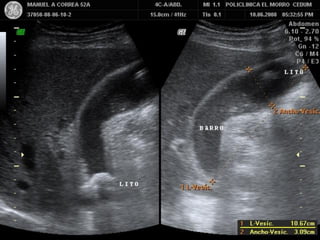

VESICULA CONTRAIDA ALREDEDOR DE

CALCULOS. COLECISTITIS CRONICA

BARRO BILIAR

HEMORRAGIA VESICULAR

OBSTRUCCION POR LITIASIS

VESICULA BILIAR NO

VISUALIZABLE

EXCLUSION QUIRUGICA / CONTRACCION FISIOLOGICA.

VESICULA ANORMAL:

V.B. CONTRAIDA ALREDEDOR DE UN CALCULO / V.B. EN PORCELANA / COLECISTITIS ENFISEMATOSA.